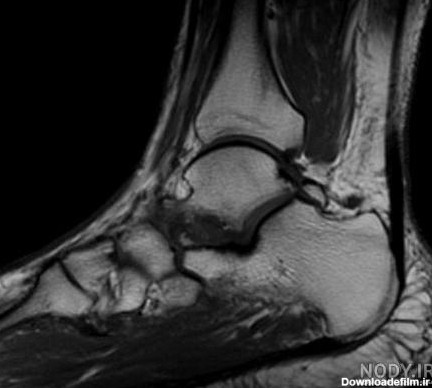

عکس ام ار ای پارگی رباط مچ پا

ام آر آی مچ پا یکی دیگر از اسکنهای شایع تصویربرداری پزشکی با ام آر آی است. در این اسکن به بررسی مچ پا ، پاشنه پا تاندون پا ، انگشتهای پا میپردازند.